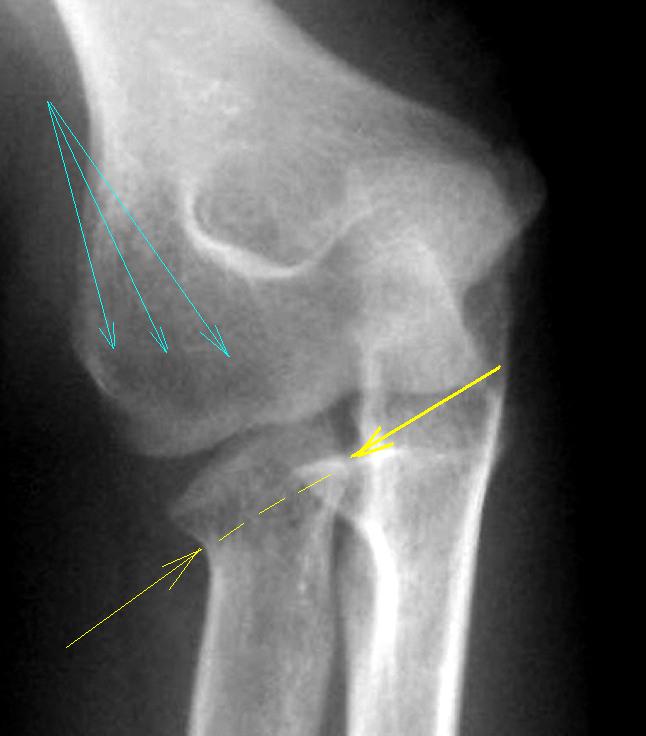

По всей видимости, была "весьма достойная травма", перелом лучевой кости (субкапитальный) с некоторым угловым смещением, что привело к некоторой угловой деформации проксимального эпи-метафиза лучевой кости. По всей видимости, остеопороз (голубые стрелки) в дистальном эпифизе плечевой кости связан с "функциональным недогрузом" в результате "уклонения" и деформации суставной поверхности головки лучевой кости.

Да и перелом локтевого отростка локтевой кости, ранее имел место быть.

Подвывих, следовательно, возник вторично.

А перелом локтевой кости, вероятно, свежий, есть симптом жировых подушечек.